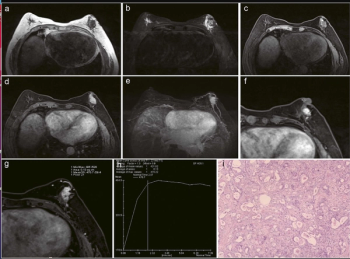

The addition of parameters such as patient age, MIP sign and associated imaging features to the Kaiser score demonstrated a 95.6 percent AUC for breast cancer detection of enhancing lesions on breast MRI in recently published research.